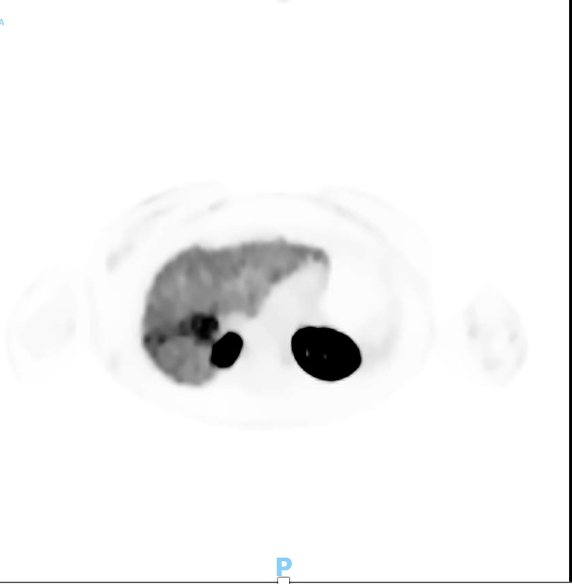

Prostate-specific membrane antigen (PSMA) PET was also performed, and findings were more consistent with hepatocellular carcinoma (HCC).